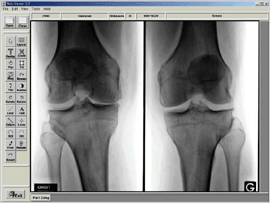

본교 의료원이 지난해 11월 LG-CNS·메디페이스와 함께 PACS(의료영상저장전송장치, Picture Archiving Communication System) 구축에 대한 계약을 체결, 시스템 구축에 들어간 것으로 뒤늦게 알려졌다. PACS란 방사선 영상 진단장치를 통해 진단한 영상을 디지털 상태로 획득, 저장하고, 판독결과와 진료기록을 함께 단말기로 전송, 검색하는 통합 의료영상시스템. 기존의 필름대신 영상정보를 디지털화한 것으로 이를 통해 서울의료원과 구리의료원간의 영상정보 호환은 물론 진료시스템에도 획기적인 변화가 올 것으로 예상된다.

서울의료원은 이르면 3월부터 구리의료원은 4월부터 가동을 시작할 예정이며 PACS 구축이 완료되어 의료원은 그야말로 필름 없는 디지털 병원으로 새롭게 거듭나게 된다. 서울의료원 홍보실 김대성씨는 "PACS를 도입함으로써 환자들에게 보다 정확한 진단이 가능해 진 것은 물론 신속한 진료를 펼칠 수 있게 됐다."고 신규 시스템의 의의를 설명했다. 시스템이 구축되면 환자는 불필요한 방사선 재촬영이 없어짐에 따라, 방사선 노출이 최소화되는 것은 물론 진료비 절감 효과와 함께 자신의 임상 정보를 바로 알 수 있는 이점이 있다.

한편 의료원측에 있어서도 새롭게 구축되는 PACS는 효자 노릇을 톡톡히 할 예정. 의료원 관계자는 "신규 서비스를 통해 필름 비용은 물론 인건비와 필름 보관비가 절감되고 미판독 이미지들의 감소, 특수검사 판독 지연 감소 등 수많은 효과를 볼 수 있다."라고 말했다. 또한 서울의료원 촬영실 부장 백종묵씨는 "잡다한 필름 관련 업무가 줄어 전공의 의학교육의 질적 향상도 기대할 수 있다."며 "무엇보다 서울과 구리가 정보 교환이 되기 때문에 보다 정확한 진료가 가능해질 것"이라 전망했다.

의료원의 의사들도 새로운 시스템의 도입을 크게 환영하는 분위기다. PACS 구축이 완료되면 의사들에게도 임상정보 증대, 즉각적인 영상이미지 확보, 불필요한 진료 감소 그리고 판독의와 임상의간의 원활한 의사교환 효과 등 다양한 편의를 제공할 것으로 보인다.

현재 구축 작업이 한창 진행중인 PACS 시스템은 서울의료원의 경우 3월 8일에, 구리는 4월 1일에 본격적인 서비스를 시작할 예정이다. 백종묵씨는 "향후 병원간 의료 영상 데이터 공유와 보안 문제, PACS의 안정적인 운용에 중점을 두고 시스템을 구축하고 있다."라며 환자와 의료원들의 편의를 의해 최선을 다 할 것이라고 말했다.